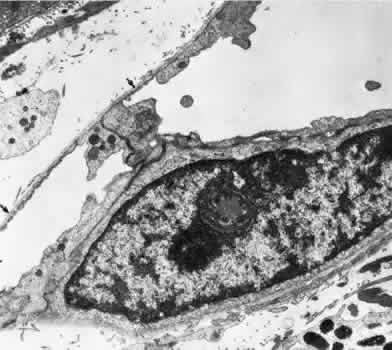

The capillaries and venules of the ciliary body are 15 to 30 μm in diameter and are fenestrated in both the pars plicata and pars plana. They closely resemble the capillaries of the choriocapillaris except that they are smaller. The fenestrae of these vessels range in size from 300 to 1,000 nm in diameter.64 The major difference between the capillaries in different areas of the ciliary body is that only those of the pars plana are in contact with the elastica of Bruch's membrane on the surface facing the pigmented epithelium. The capillaries present in the ciliary muscle are nonfenestrated (Figs. 16 and 17). The blood vessels are innervated by small branches of sympathetic fibers.

Fig. 16. Electron micrograph of a portion of a capillary facing the stroma of the ciliary process. The endothelial cell contains moderate amounts of rough-surfaced endoplasmic reticulum and numerous pinocytotic vesicles and few fenestrae. A very thin basement membrane is present. Particles of thorium dioxide may be seen in the lumen (l). This specimen was taken from a rat.

Fig. 17. Electron micrograph of a portion of a capillary from the ciliary process facing the pigmented epithelium (p). Note the absence of an elastic lamina between the vessel and the pigmented epithelium. Fenestrae are present, and the endothelium is quite attenuated. This specimen was taken from a rat injected with thorium dioxide. l, capillary lumen.